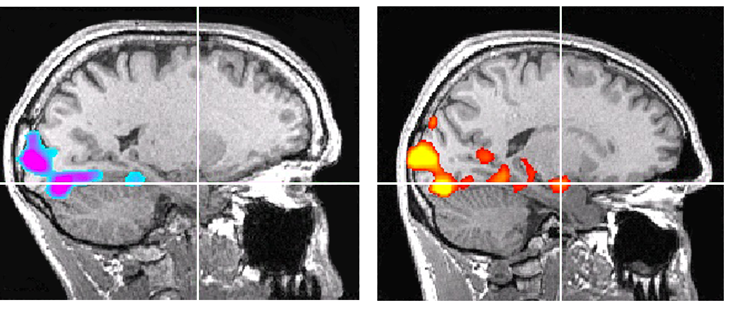

Проф. Джейн Джоузеф реши да изследва мозъка на Алекс Хонълд с метода на магнитния резонанс. В хода на изследването на катерача беше показана серия от 200 снимки, която у средно статистически изследван предизвиква активизация на т. нар. бадемовидно тяло (амигдала) на мозъка. То отговаря за генерирането на негативните емоции, агресията и защитните реакции – като, например, страха. Как е изглеждала реакцията на Хонълд, се вижда на долната снимка.

Снимки на мозъка на Алекс Хонълд (вляво) и на друг катерач на същата възраст.

Пресичащите се линии показват положението на бадемовидното тяло, а цветните петна –

неговата активност...

Проф. Джейн Джоузеф реши да изследва мозъка на Алекс Хонълд с метода на магнитния резонанс. В хода на изследването на катерача беше показана серия от 200 снимки, която у средно статистически изследван предизвиква активизация на т. нар. бадемовидно тяло (амигдала) на мозъка. То отговаря за генерирането на негативните емоции, агресията и защитните реакции – като, например, страха. Как е изглеждала реакцията на Хонълд, се вижда на долната снимка.

Снимки на мозъка на Алекс Хонълд (вляво) и на друг катерач на същата възраст.

Пресичащите се линии показват положението на бадемовидното тяло, а цветните петна –

неговата активност...